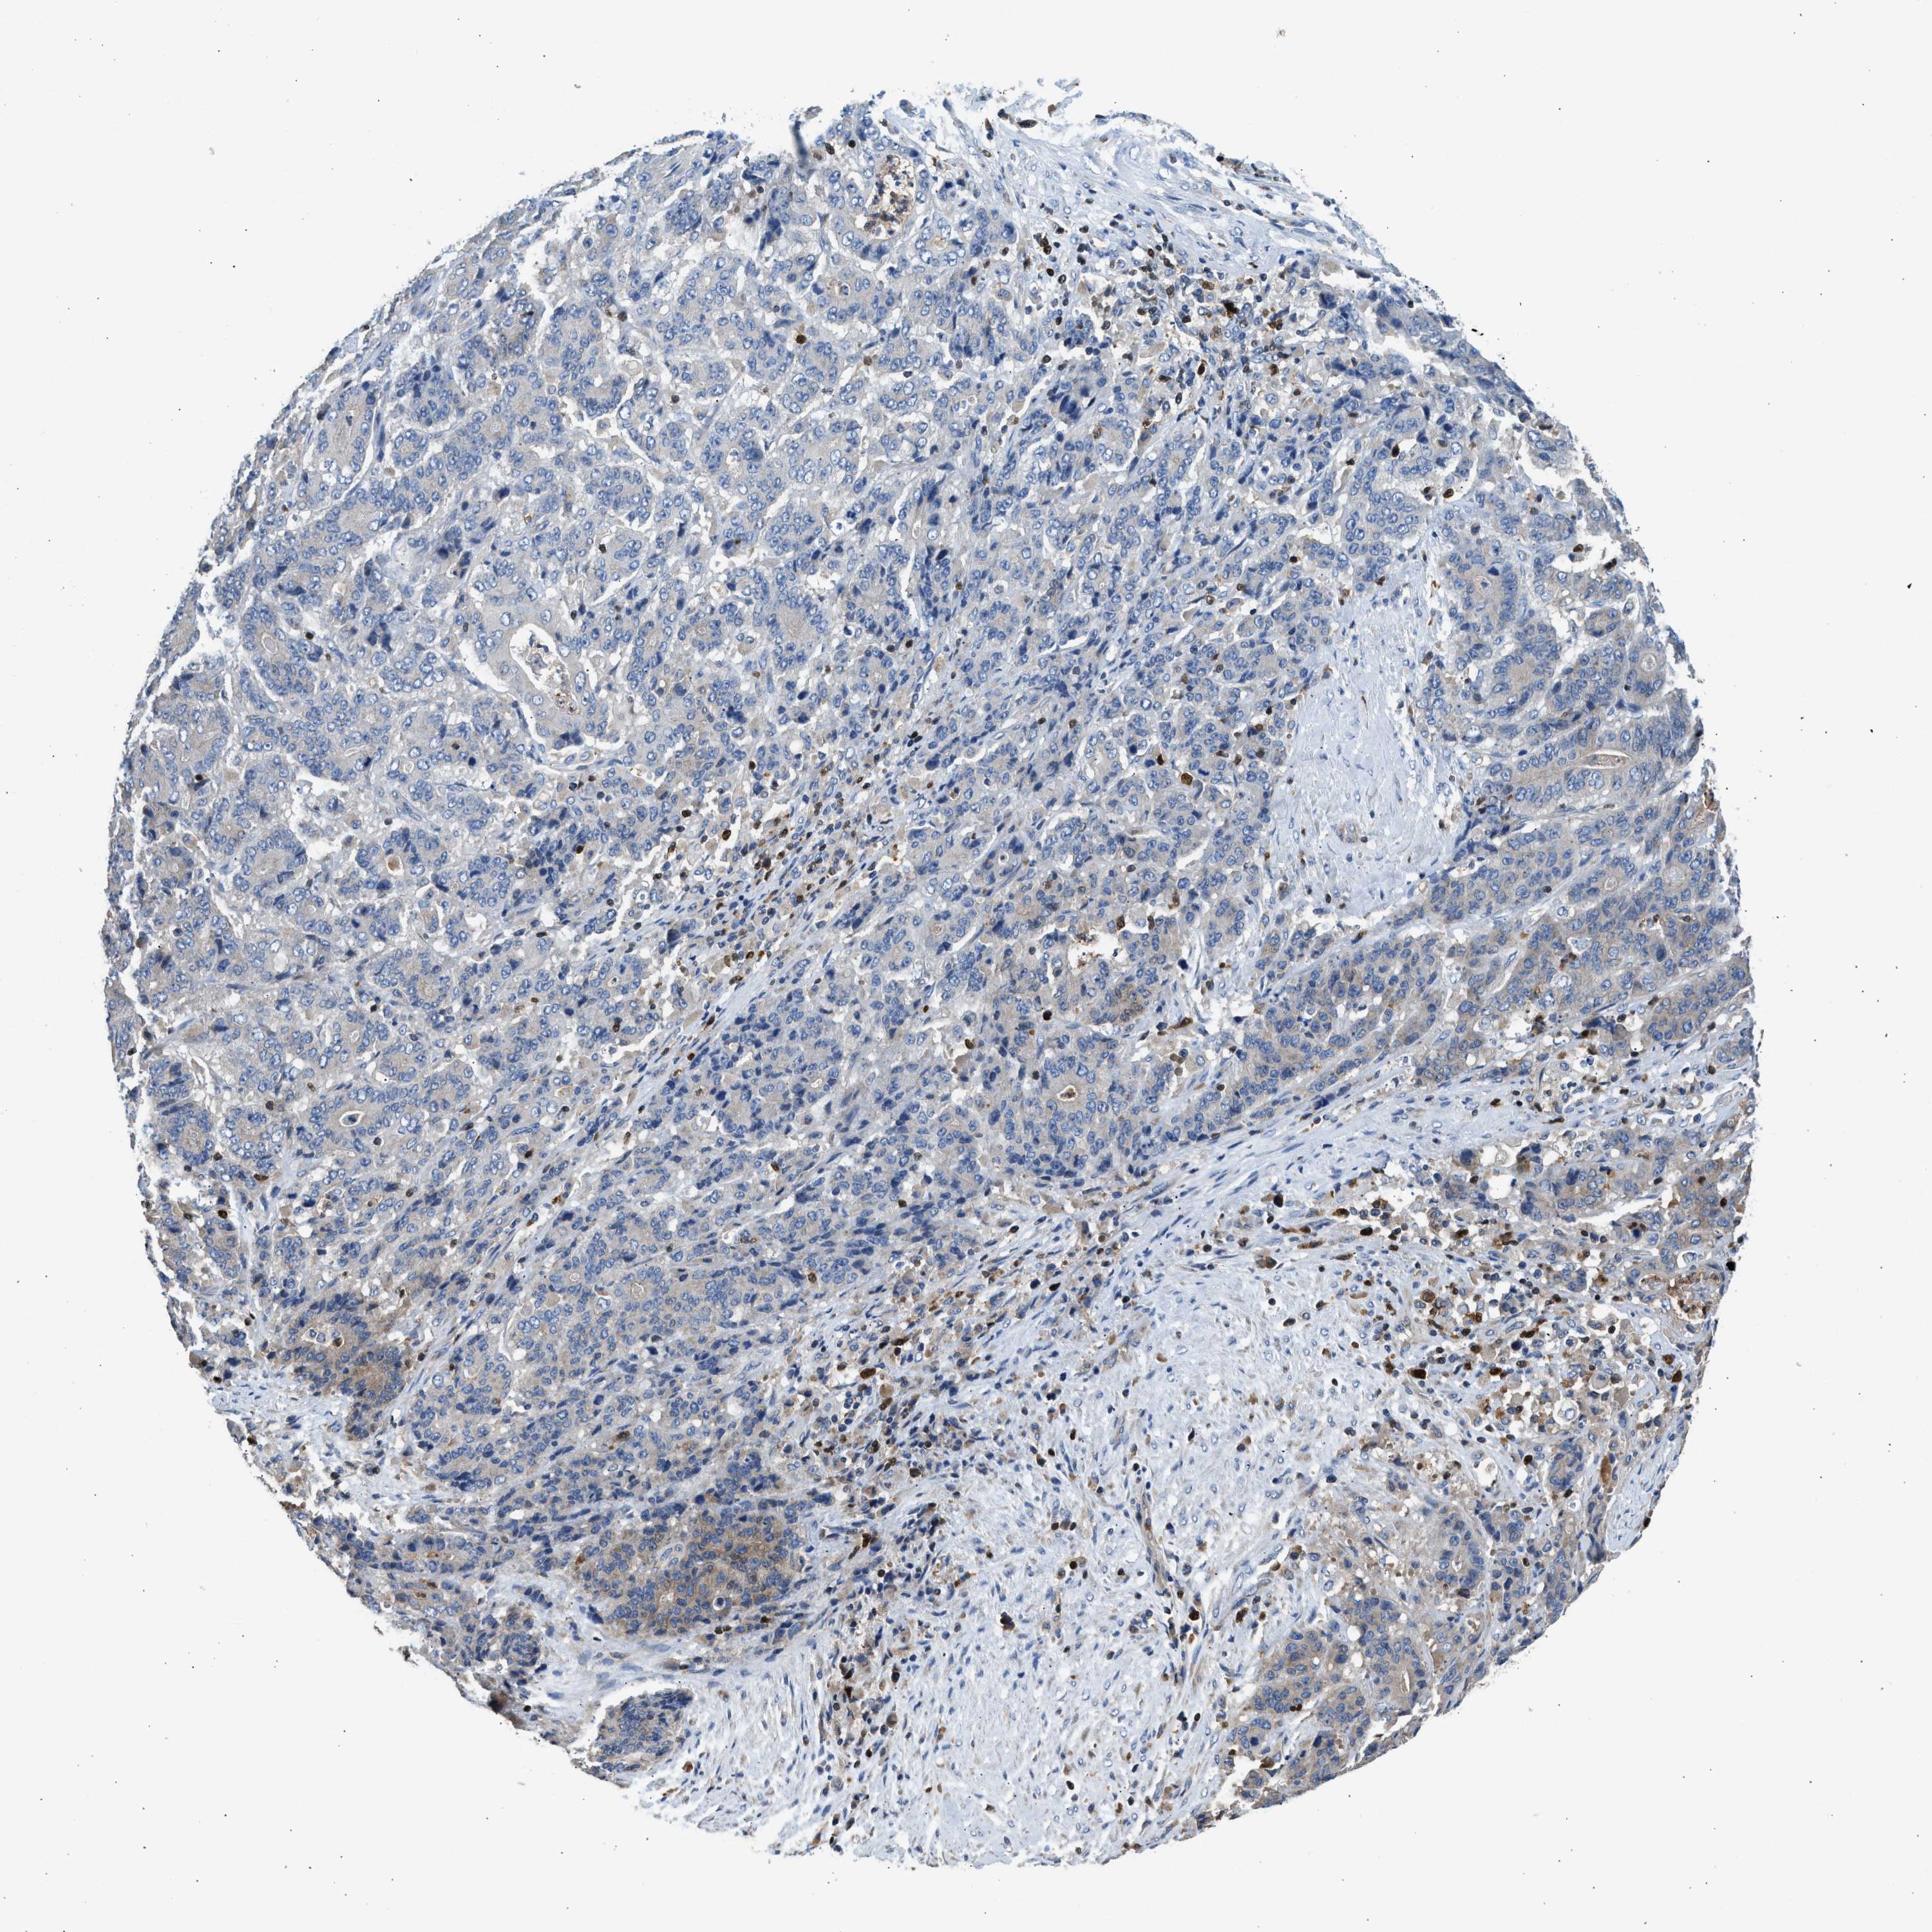

STOMACH CANCER - Protein expressioni

A mouse-over function shows sample information and annotation data. Click on an image to view it in a full screen mode. Samples can be filtered based on level of antibody staining by selecting one or several of the following categories: high, medium, low and not detected. The assay and annotation is described here.

Note that samples used for immunohistochemistry by the Human Protein Atlas do not correspond to samples in the TCGA dataset.

Antibody stainingi

Antibody staining in the annotated cell types in the current human tissue is reported as not detected, low, medium, or high, based on conventional immunohistochemistry profiling in selected tissues. This score is based on the combination of the staining intensity and fraction of stained cells.

Each image is clickable and will lead to virtual microscopy that enables deeper exploration of all samples and also displays staining intensity scores, fraction scores and subcellular localization as well as patient and tissue information for each sample.

Antibody HPA018322

Staining

High

Medium

Low

Not detected

Intensity

Strong

Moderate

Weak

Negative

Quantity

>75%

75%-25%

<25%

None

Location

Nuclear

Cytoplasmic/membranous

Cytoplasmic/membranous,nuclear

Adenocarcinoma, NOS